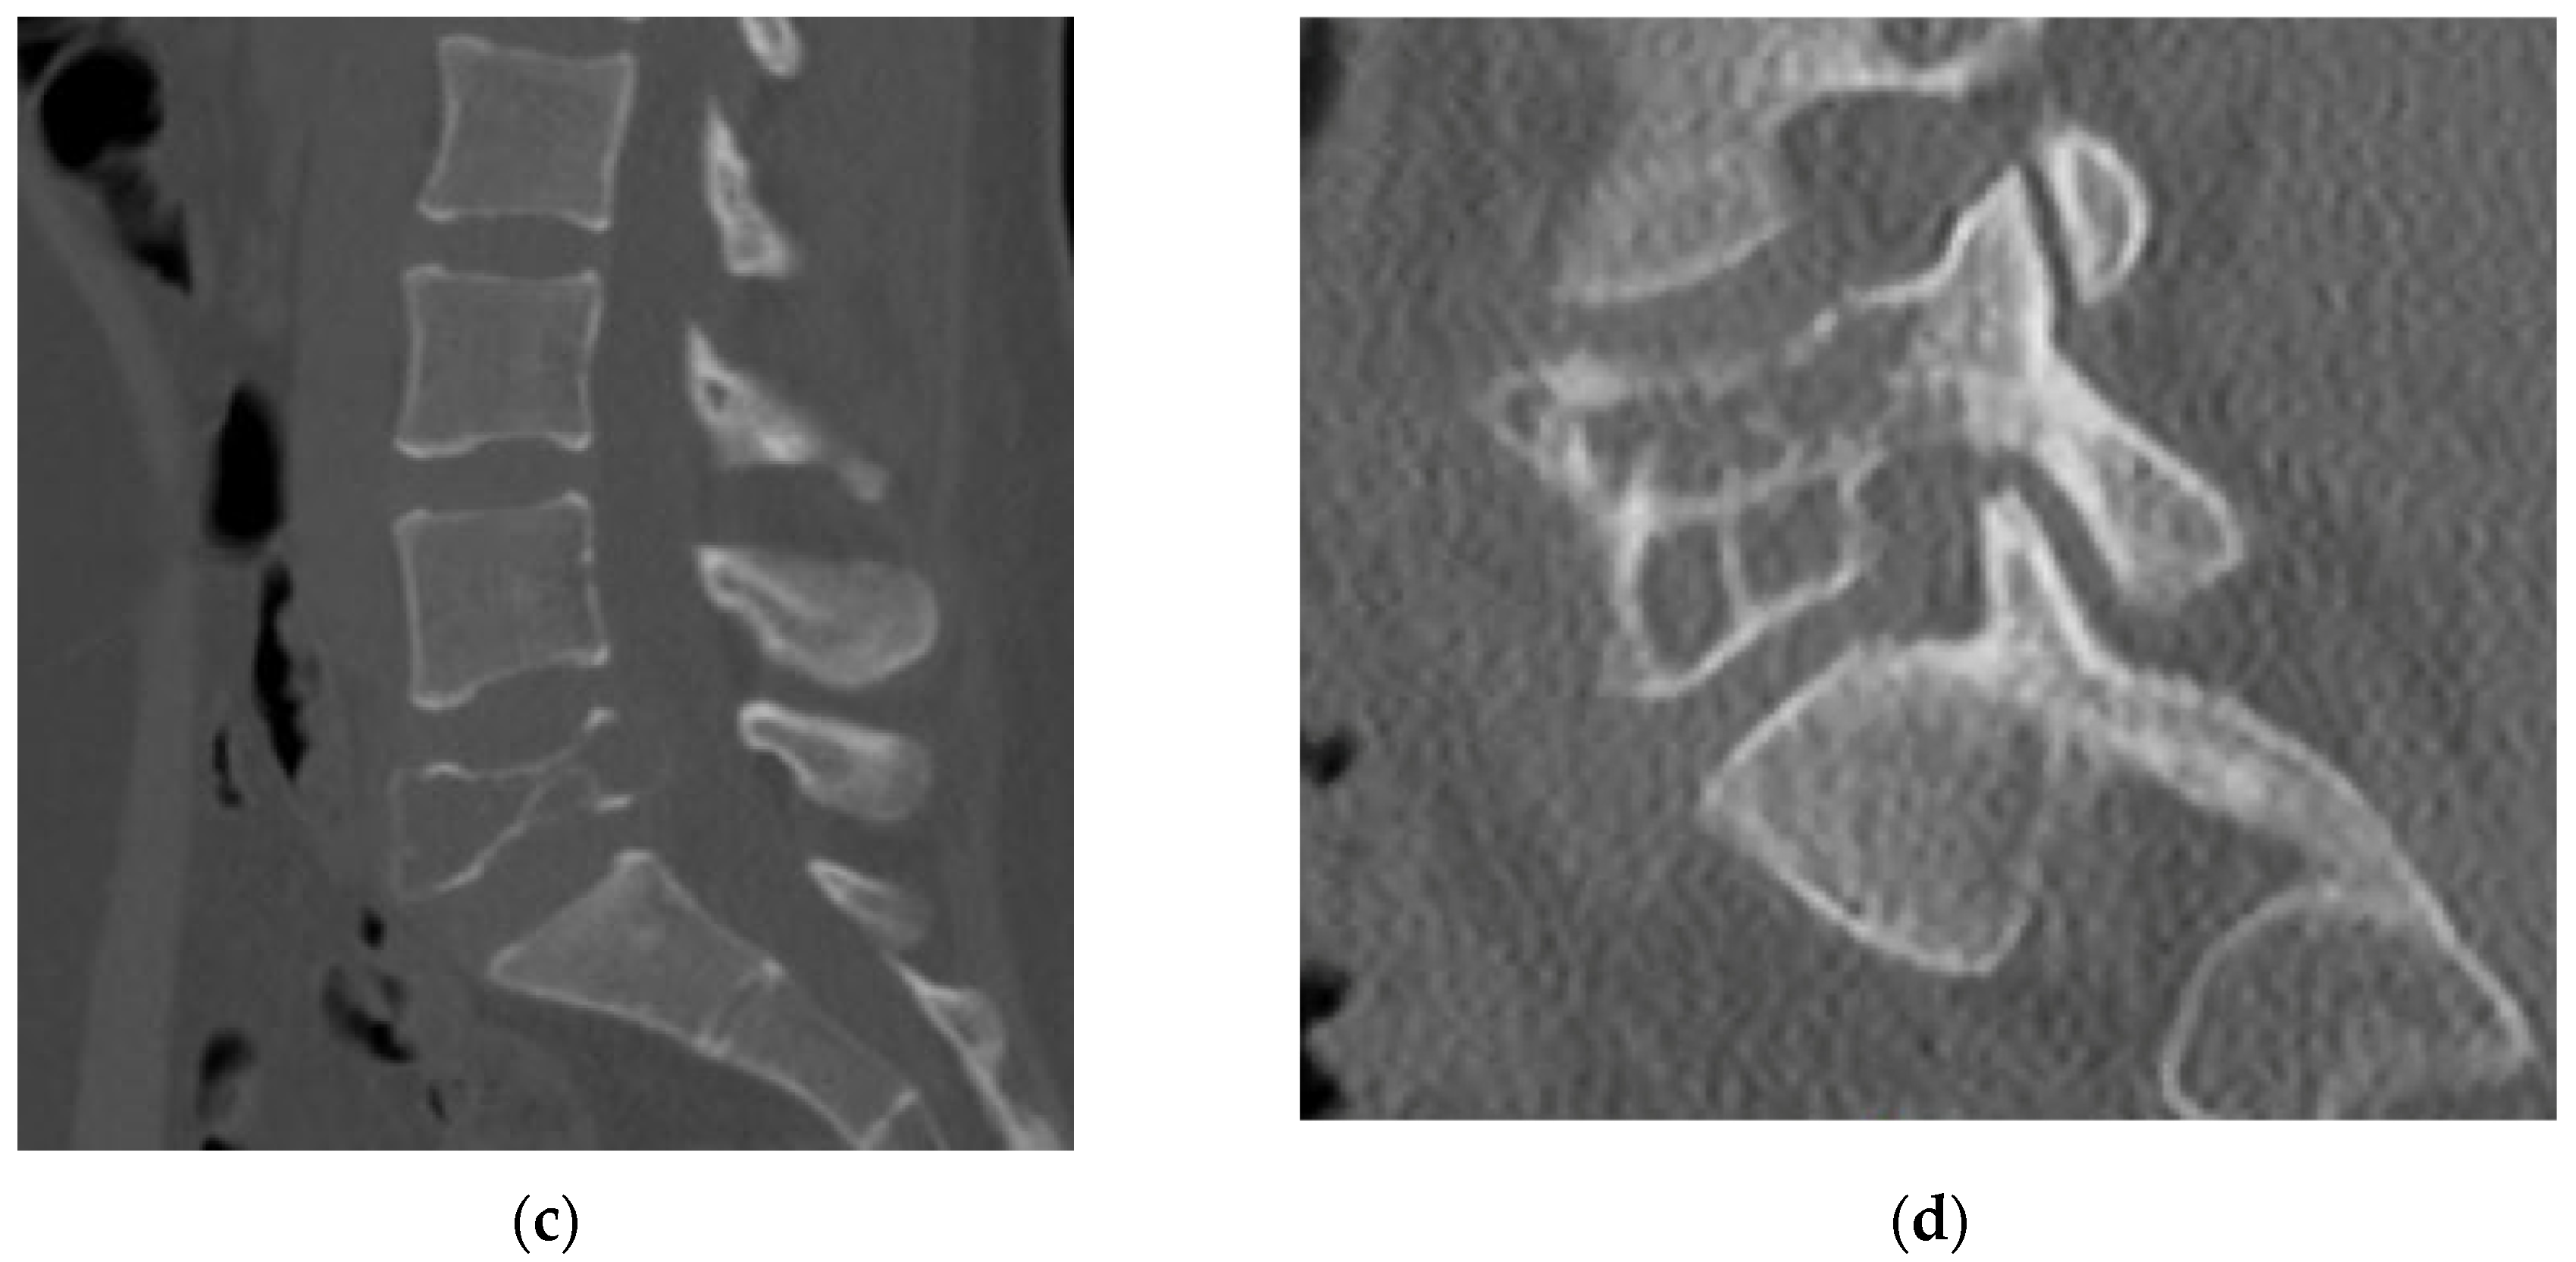

4.2.4. Computerized Tomography Scan